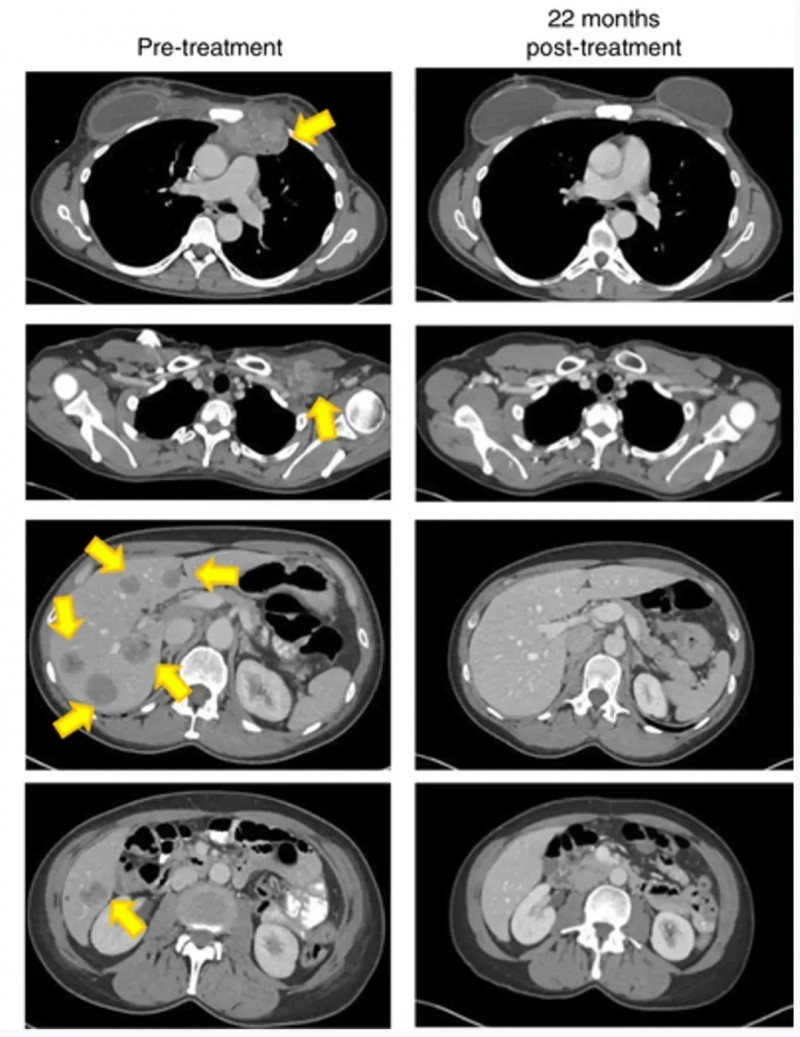

《Nature Medicine》报道了一例振奋案例(NCT01174121):一名难治性激素受体(HR)阳性转移性乳腺癌患者,经特异性肿瘤浸润淋巴细胞(TIL)联合治疗后,肿瘤实现完全持久消退,截至报道已持续22个月以上。

本例患者是一位49岁女性,确诊为雌激素受体(ER)阳性、HER2阴性转移性乳腺癌,对多种化疗及内分泌疗法耐药。入组后接受TIL细胞+白细胞介素-2(IL-2)+检查点阻断联合治疗。

结果显示:细胞回输后6周,靶肿瘤负荷减少51%;细胞移植22个月时,所有靶病变及非靶病变均实现放射学完全消退(详见下图)。

▲图源“Nat Med”,版权归原作者所有,如无意中侵犯了知识产权,请联系我们删除